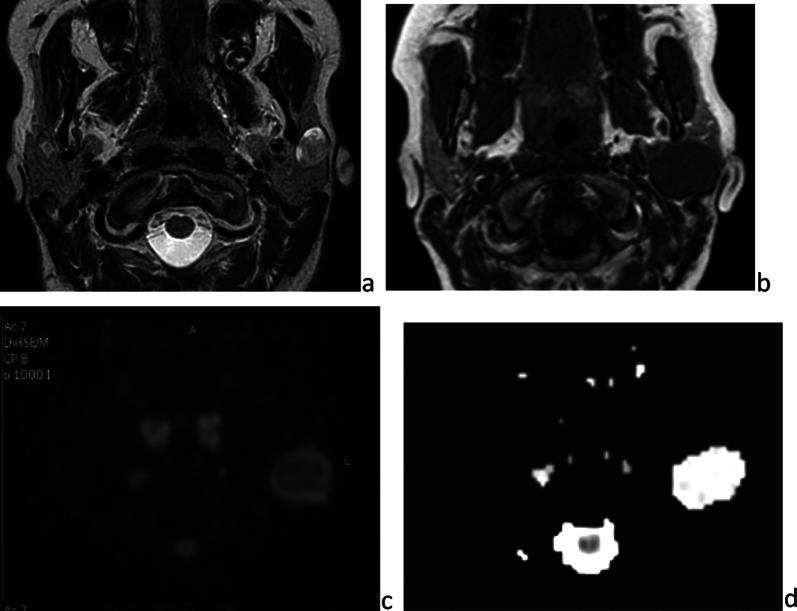

在婴幼儿及儿童时期,多种疾病可累及腮腺。急性或慢性炎症/感染性疾病最为常见。第一鳃裂畸形是先天性病变,通常在儿童期出现。肿瘤性病变多为良性,婴儿期最常见的是婴儿血管瘤,儿童期最常见的是多形性腺瘤。恶性肿瘤并不常见,黏液表皮样癌相对多见。腮腺浸润性疾病罕见,且具有一些儿科临床特点。本文对儿童期腮腺这些常见和不常见疾病及其影像学特征进行综述。